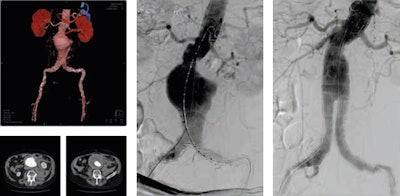

He thinks retroperitoneal hematoma adjacent to an abdominal aortic aneurysm is the most common imaging finding indicative of aneurysm rupture. Endovascular aneurysm repair (EVAR) has become an established technique for the treatment of many infrarenal aortic aneurysms. Less invasive than open surgical repair, EVAR is associated with better outcomes, according to Pyra (see figures 1 and 2).

Figure 1 (above): Ruptured abdominal aortic aneurysm before and after stent graft implantation. Figure 2 (below): Ruptured abdominal aortic aneurysm: classical surgery versus percutaneous stent graft implantation under fluoroscopy guidance. Images courtesy of Dr. Krzysztof Pyra.The interventional radiologist's remit also rests on the repair of other relatively common pathologies; acute aortic dissection, for example, occurs when blood enters the medial layer of the aortic wall through a tear or penetrating ulcer in the intima and tracks along the media, forming a second blood-filled channel within the wall.